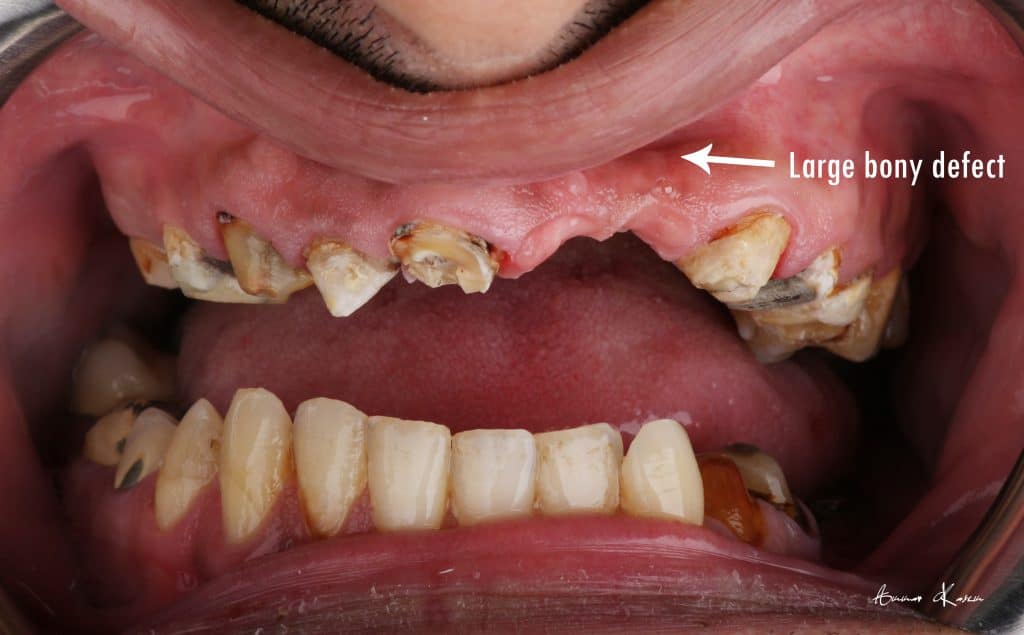

The patient was normally class I occlusion type ( according to old photos and cephalometric analysis) till he received this defective restorations 10 years ago

With time, the mandible shifted till become habitual class III

The patient was diagnosed by orthodontist, oral surgeon and prosthodontist to make the best treatment plan